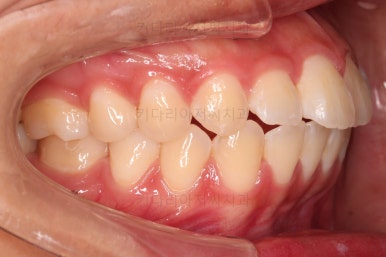

1. 초진 시 입안의 모습 평가

부산연산역치아교정 키다리아저씨치과에 처음 내원했을 당시의 입안의 모습이비다.

앞니 약간, 어금니쪽 약간 삐뚤어진 것, 그리고 위아래 앞니가 약간 뻗쳐 보이는 양상 이외에는 매우 가지런해 보여서 교정치료를 굳이 왜 하시려고 하지? 라고 생각될 정도의 치열 상태였습니다.

웃거나 말할 때 드러나는 치열의 모습도 굉장히 가지런한 편에 속하는데요.

앞니쪽이 뻐드러진 느낌, 그래서 부각되어 보이는 양상이었고요.

입을 다물었을 때, 특유의 돌출감으로 입술 주위 ~ 턱끝 주위에 힘이 들어가서 입매가 어색해 보이는 특징이 있었습니다.